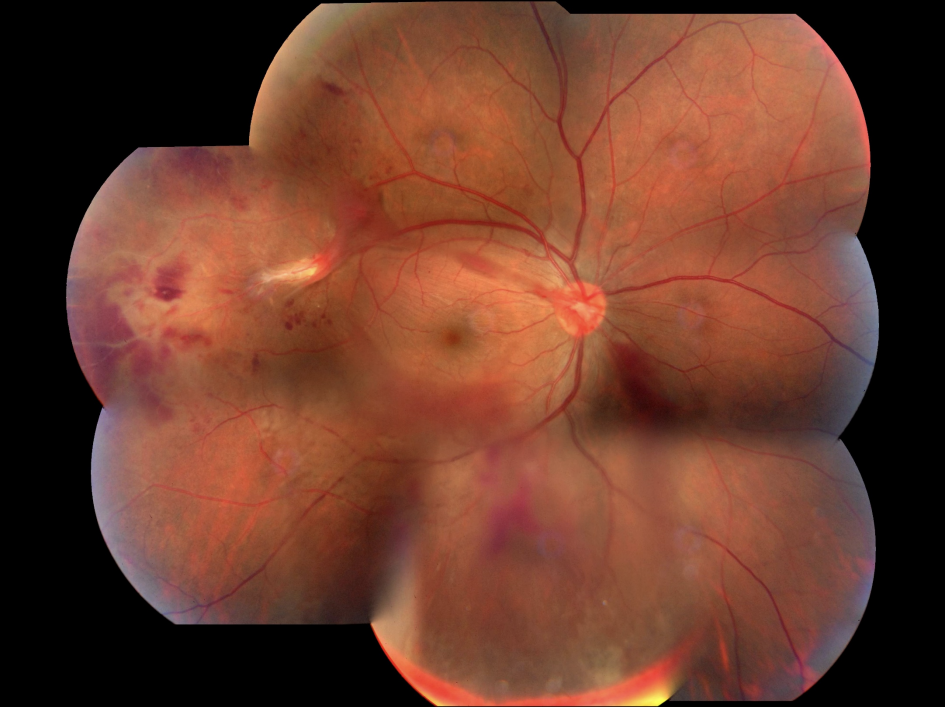

視網膜血管發炎

視網膜血管發炎。